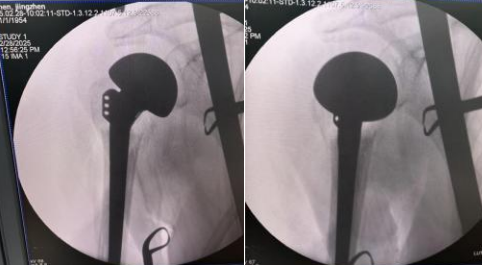

术中攻坚:精准施治,技艺精湛

2 月 28 日,手术当日,在麻醉科与手术室的全力配合下,王建华主任带领团队为患者实施手术。术中发现骨折情况比预期更为严重,肱骨头碎裂,多块关节面游离且脱位,骨质疏松骨缺损明显,复位内固定已不可能,果断决定行半肩置换术。凭借丰富的经验与精细操作,王主任精准恢复肱骨头高度与后旋角度,原位固定修复了大小结节,恢复了肩袖的完整性及功能,重建了患者的肩关节动力系统。